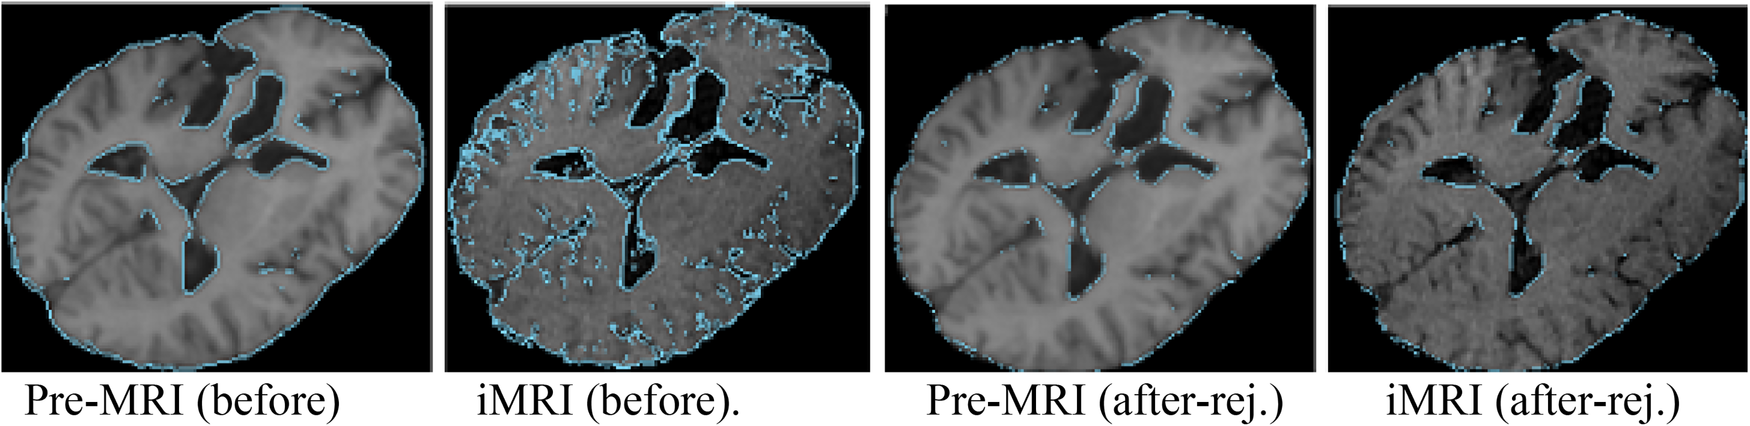

NEMNRR addressed a fundamental challenge in PBNRR: “pre-operative landmarks near the tumor fail to correspond to iMRI landmarks”. The crux of the idea is to use the NEM method to resolve the deformation field with missing correspondence, specifically in the resection region. This has many implications; one is to compute the registration error more accurately than Hausdorff Distance (HD) when correspondence is unknown. Like the PBNRR, the NEMNRR uses the strain energy of the biomechanical model to regularize the solution. Figure 5 shows the results of point outlier rejection produced by NEMNRR; compared to the edges before outlier rejection, most point outliers are removed from pre-MRI and iMRI after outlier rejection.

Figure 5

Point outlier rejection. Two left-most pre-op and iMRI depict (in blue) all edges detected before rejecting outliers, while the right-most figures depict the remaining edge points after outlier rejection.